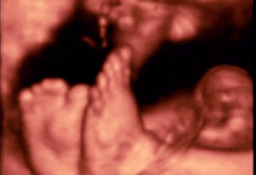

En la ecografía del tercer trimestre es muy difícil extraer una imagen completa del bebé. Rara vez se las apaña el ecografista para poder captar una "foto panorámica" de una criatura, que ya ocupa casi la totalidad del útero materno. Por eso, la mayoría de las ecos de esta edad gestacional se especializan en partes u órganos específicos del feto. El ecografista puede detectar aún ciertas anomalías del desarrollo, comprueba el líquido amniótico, el bienestar fetal y, muy importante, visualiza el cordón umbilical, que puede estar enrollado en algún órgano como cuello, pies o manos.